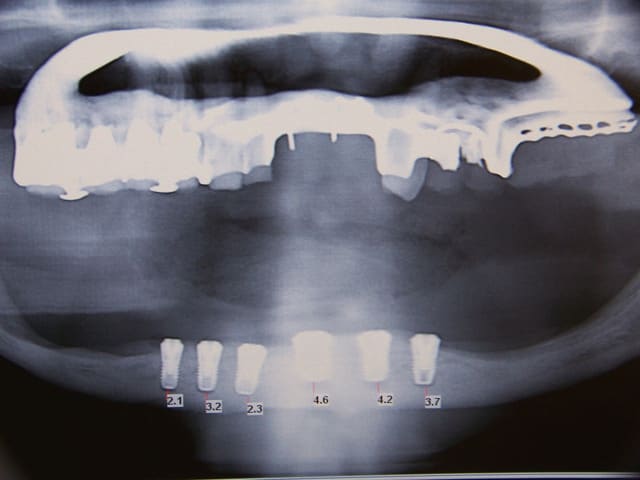

Mais comme son amie me fait une bonne pub elle se decide à passer son scanner et voila le resultat.

au maxillaire sans greffe d'apposition osseuse je ne vois pas comment faire quelque chose de correct,et à la mandibule à part deux implant symphisaire et locator je sais ps comment faire. J'aurai bien aimé un all on 4 pour eviter de trop appuyer sur les cretes tres resorbées en posterieur avec nerf quasiment sur la crete,

mais meme deux implant la je suis moyen chaud, n y aurait il pas un risque de fracture?

quelle est la hauteur d'os disponible au niveau symphysaire?

en bas 5 implants symphysaires et en haut, greffes d'apposition pour 4 implants de chaque côté.